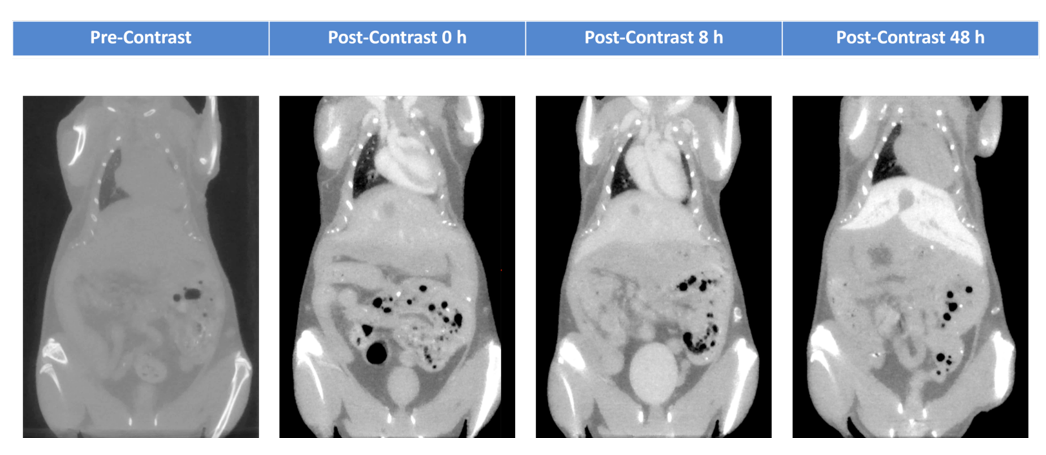

活体小鼠在注射Fenestra HDVC后

活体小鼠在注射Fenestra HDVC后,48小时内获取不同时间点的micro-CT图像。 产品应用咨询:戴老师 13751019367

| 描述: | Fenestra-HDVC 是一种碘化纳米乳液,用于脉管系统、肝脏和脾脏的 microCT 成像。与以前的 Fenestra 配方相比,该产品的碘剂量 (100 mgI/ml) 是以前的两倍,使研究人员能够减少注射剂量。 Fenestra-HDVC 在血液中循环 24 小时,以便进行血管成像。在血液中 4 小时后,它开始选择性地靶向肝细胞。 24 小时后,它可以进行肝脏解剖成像、分期和监测脂肪肝疾病,以及量化肝脏肿瘤负担。 Fenestra-HDVC 在单次注射后会在肝脏中保留数月,并能够对肝脏疾病进行纵向研究。 |